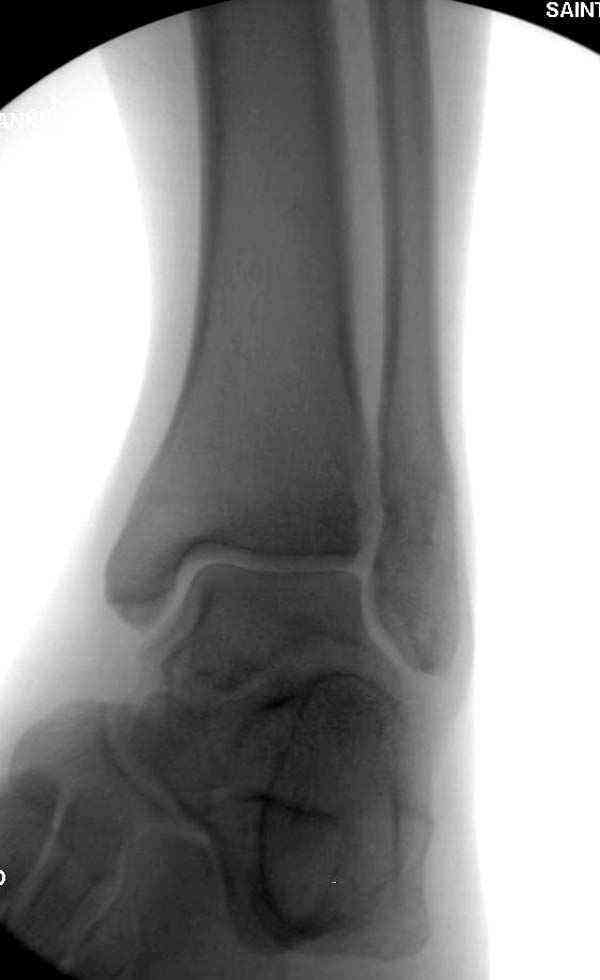

Достаточно быстрое восстановление функции.В октябре 2009г-почувствовала боль,в области рубца над гайкой открылся свищ.На Р-граммах-консолидация переломов и смещение гайки по стяжке.10.11.2009г-конструкции удалены,санация,заживление ран.В настоящее время пациентку ничего не беспокоит.На операции-раскручивание гайки-болталась на конце стяжки.Вопросы:какой механизм раскручивания и что я неправильно сделал?Свои версии:1)в области синдесмоза успела образоваться рубцовая ткань,которая при движении в суставе"пружинила",поскольку голеностопный сустав является спиральным, то и биомеханика подобна кривошипному механизму.2)Реконструктивная пластина не "реконструировалась" по форме лодыжки.Наложил,как есть.То есть подпружинивала сама пластина.Ну,это мои догадки.Что нужно,чтобы избегать впредь таких,пусть и не "страшных"осложнений:Рассверливать через лодыжку область синдесмоза?Ставить шайбу-гровер?Тщательно моделировать пластину?Прилагаю сравнительные снимки-сразу после операции и перед удалением конструкции.

Визуально никаких вопросов по репозиции не было.Да и на основании чего сомнения,что наружная лодыжка не полностью репонирована или прорезалась проволка ???Я не вижу...Снимок после репозиции справа.

Здесь несколько частных случаев: перелом голеностопа со сравнительными снимками и разрыв синдесмоза, а также медиальная Hook пластина.